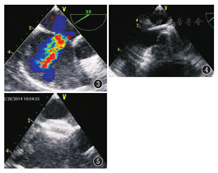

经TEE检查后适合封堵者,更换为左侧90°卧位,左腋下垫高,右上肢外展90°~120°,右肘关节屈曲90°悬吊固定在麻醉架上,沿腋中线在第3肋骨上缘和第5肋骨下缘之间做垂直的2~3 cm切口,切口长度根据患者的身高和体质量有所不同。经第4肋间进胸,放置肋骨牵开器,湿纱布推开右肺,于膈神经前方2 cm纵形切开心包,并尽量向外悬吊心包,暴露右心房。肝素化(1 mg/kg),5-0 Prolene线在右心房外侧中部缝单荷包。将肝素盐水浸泡后的封堵器旋于推送杆上,拉直收拢,纳入输送鞘管,通过侧支管打水排气,一般选取较ASD最大伸展径大0~4 mm的封堵器。右心房荷包内穿刺,插人输送鞘管,通过侧支管向外抽吸血液再次排气。TEE引导下,将封堵装置通过缺损送入左心房(早期技术不熟练者,需要先用可塑性的中空鞘管建立输送轨道)。于ASD两侧分别释放出两伞封闭ASD。术中注意不可将封堵器过早脱离推送系统,当封堵器夹住ASD缘后,在食管超声心动图监测下推拉封堵器,测试封堵器牢固程度,食管超声心动图确认封堵器位置形态良好,对二尖瓣及三尖瓣启闭无影响,上、下腔静脉及冠状静脉窦开口血流通畅,无残余分流,无心律失常发生,即可释放封堵器撤出推送杆和鞘管,再次观察封堵器形态及位置无异常后,方可剪断封堵器牵引线,结扎心房荷包缝线,必要时加固缝合,防止心房穿刺口渗血。常规止血及胸腔排气后关胸,术后一般不用鱼精蛋白中和肝素,可放置胸腔引流管,防止大量气胸或胸腔积液发生(图1,图2,图3,图4,图5)。

经右腋下封堵成功28例,有2例因房间隔缺损较大和下缘太短封堵不成功,而经原切口改行体外循环修补手术,其余全部封堵成功,1例首次安放不牢固,术中更换大号封堵器;2例双孔ASD采取大号封堵器经大孔一次性封堵成功;有2例操作过程中分别出现房性和室性期前收缩,释放成功过后自行恢复正常;有1例早期因操作不熟练失血较多予术中输血,其余均未输血;早期常规不放置胸腔引流管,后有1例患者术后出现右侧胸腔大量积液,予穿刺置管引流,之后常规放置胸腔引流管。心内操作时间3~20(5.0±3.5)min,缺损大小5~16(8.4±2.6)mm,封堵器大小8~20(10.8±3.3)mm,呼吸机使用时间2~4(3.0±0.7)h,术后引流量5~20(12±4)mL,切口大小2~4(3.0±0.7)cm。封堵成功患者均于术后5~9 d出院。